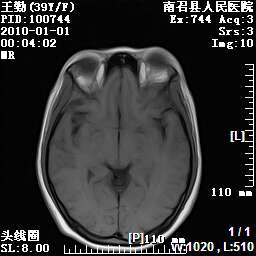

以下是引用随光逐影在2010-1-22 9:03:00的发言:[br]考虑左侧中颅窝(蝶骨翼区)脑膜瘤侵犯蝶骨翼并突入左侧眼眶。

以下是引用水过无痕在2010-1-22 14:55:00的发言:[br]一、定位:颅外占位;二、定性:恶性可能性大;三、组织来源:来源于左侧眼外直肌或其他部位;考虑为:横纹肌肉瘤>转移瘤>脑膜瘤.